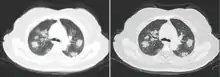

Chest CT scans may be helpful to diagnose COVID‑19 in individuals with a high clinical suspicion of infection but are not recommended for routine screening.[134][146] Bilateral multilobar ground-glass opacities with a peripheral, asymmetric, and posterior distribution are common in early infection.[134][147] Subpleural dominance, crazy paving (lobular septal thickening with variable alveolar filling), and consolidation may appear as the disease progresses.[134][148] Characteristic imaging features on chest radiographs and computed tomography (CT) of people who are symptomatic include asymmetric peripheral ground-glass opacities without pleural effusions.[149]

Many groups have created COVID‑19 datasets that include imagery such as the Italian Radiological Society which has compiled an international online database of imaging findings for confirmed cases.[150] Due to overlap with other infections such as adenovirus, imaging without confirmation by rRT-PCR is of limited specificity in identifying COVID‑19.[149] A large study in China compared chest CT results to PCR and demonstrated that though imaging is less specific for the infection, it is faster and more sensitive.[133]